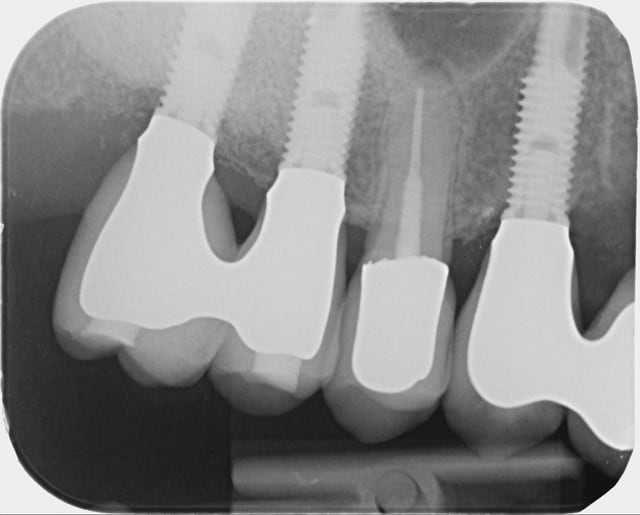

07/11/2014 à 09h39

la suite...

G 21 janvier 2011 xurlrw - Eugenol

H 19 fevrier 2013 tvy4db - Eugenol

I  21 janvier 2014 gyys5o - Eugenol

J 21 mai 2014 i8zdgv - Eugenol

Jj 16 octobre 2014 clat7g - Eugenol

Jjj 16 otobre 2014 yevkyg - Eugenol